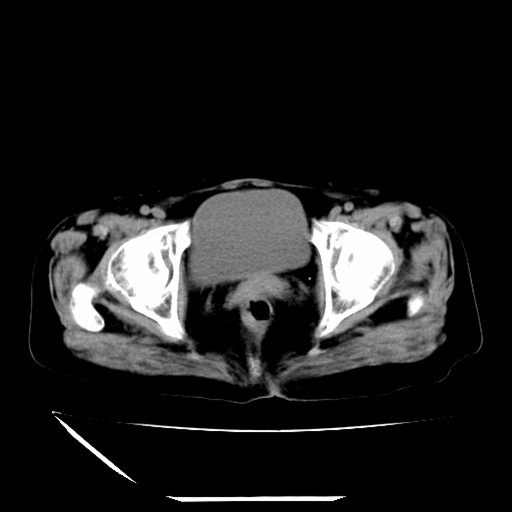

标题: CT16840:女-63岁,下腹部疼痛, [打印本页]

标题: CT16840:女-63岁,下腹部疼痛,

补充资料:血象是13.5,临床拟诊阑尾炎

本人诊断是右肾周围炎,阑尾炎,盆腔少许积液!

我觉得你的诊断欠妥;1)右肾周围炎症?是个什么诊断?2)明显的阑尾炎也没看到,最好不要这样写,就是道格拉斯窝内少量积液。

道格拉斯窝内少量积液。

支持 阑尾炎,盆腔少量积液。